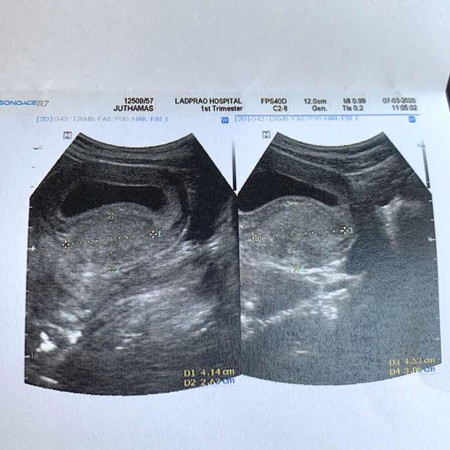

ซาวด์ครั้งแรก 9w 1d หมอบอกเจอเนื้องอก แต่ไม่เป็นอันตราย

แม่ๆบ้านไหน ซาวด์แล้วเจอเนื้องอกบ้างไหมคะ ตอนแรกเป็นกังวล แต่หมอบอกไม่เป็นอันตราย เลยทำใจให้สบาย หมอว่าหลังคลอดค่อยดูอีกทีว่าต้องทำยังไง